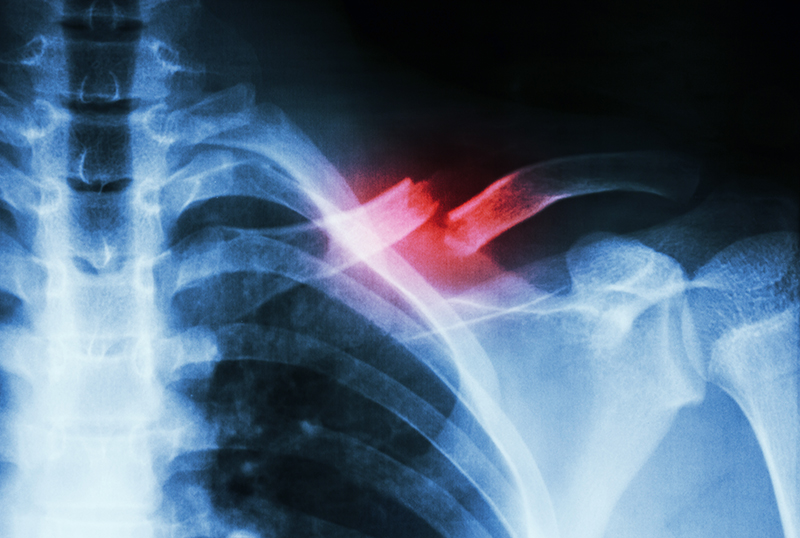

To better understand the risk factors that contribute to the failure of fractured bones to heal, a national team of orthopaedic surgeons examined health records from 90.1 million patients. Their goal was to describe the epidemiology of fracture nonunion in adults using the information available to physicians at patient presentation. They focused on patients 18-63 years old, representing 6,725 patients with 309,330 fractures. They researched risk factors likely to be of general concern to orthopaedic surgeons and pooled data to identify 45 variables of interest.

The researchers found a nonunion rate of 4.93% overall with substantial variation from bone to bone. The lowest nonunion bone rates were in metacarpal at 1.47% and radius at 2.10%. The highest nonunion rates were in scaphoid at 15.46%, tibia+fibula at 13.95%, and femur at 13.86%.